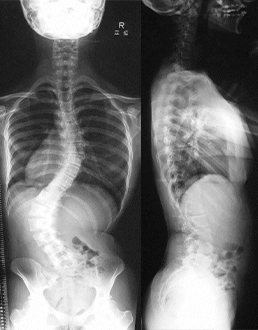

1. 側弯症手術

背中側を切開して椎骨の後方に椎弓根スクリューという金属を挿入して変形を矯正する手術を行います。椎弓根スクリューによる変形矯正は従来の方法に比べ良好な矯正が可能です。ナビゲーションシステムを導入して、正確に椎弓根スクリューを挿入できるように安全対策を行っております。また手術中は常に脊髄に電気を流し、脊髄神経の障害が起きていないかをリアルタイムに確認できる脊髄モニタリングも行いながら手術を行っており、手術治療の安全性はかなり高くなっております。

症例:特発性側弯症